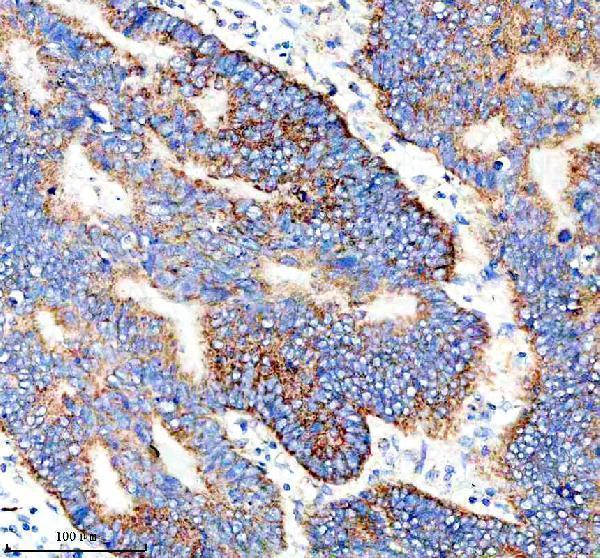

As a member of the NUPR1/RELB/IER3 survival pathway, can offer pancreatic ductal adenocarcinoma with remarkable resistance to cell stress, such as starvation or gemcitabine therapy. .

| Gene Name: | IER3 |

DIF-2; DIF2GLY96; Differentiation-dependent gene 2 protein; expressed in pancreatic carcinoma; gly96, mouse, homolog of; IEX-1; IEX1death protein; IEX-1L; Immediate early protein GLY96; Immediate early response 3 protein; immediate early response 3; immediately early gene X-1; PRG1PACAP-responsive gene 1 protein; Protein DIF-2; Protein PRG1; radiation-inducible immediate-early gene IEX-1

Membrane; Single-pass type II membrane protein.